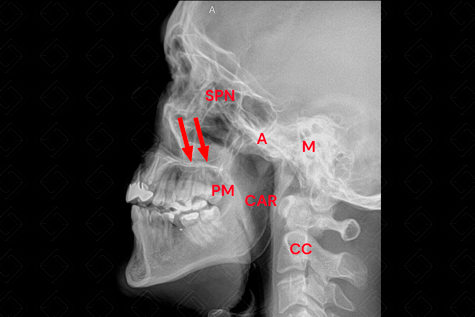

Texto alternativo para a imagem Anatomia na radiografia de cavum. Créditos: Athena Hub/Medical Harbour

Legenda: A = adenoide; CAR = coluna aérea rinofaringe; [cms-watermark] [cms-watermark] CC = coluna cervical; M = mastoide; PM = palato mole [cms-watermark] ; SPN = seios paranasais; setas vermelhas = palato duro.

Para a adequada avaliação da radiografia do cavum, é necessária a presença somente da coluna aérea da rinofaringe. Comumente, por erro técnico, vemos as duas colunas: da orofaringe e rinofaringe, prejudicando a avaliação radiológica. Diante dessa situação, cabe ao médico radiologista solicitar que o técnico repita o exame com a criança realizando inspiração nasal.